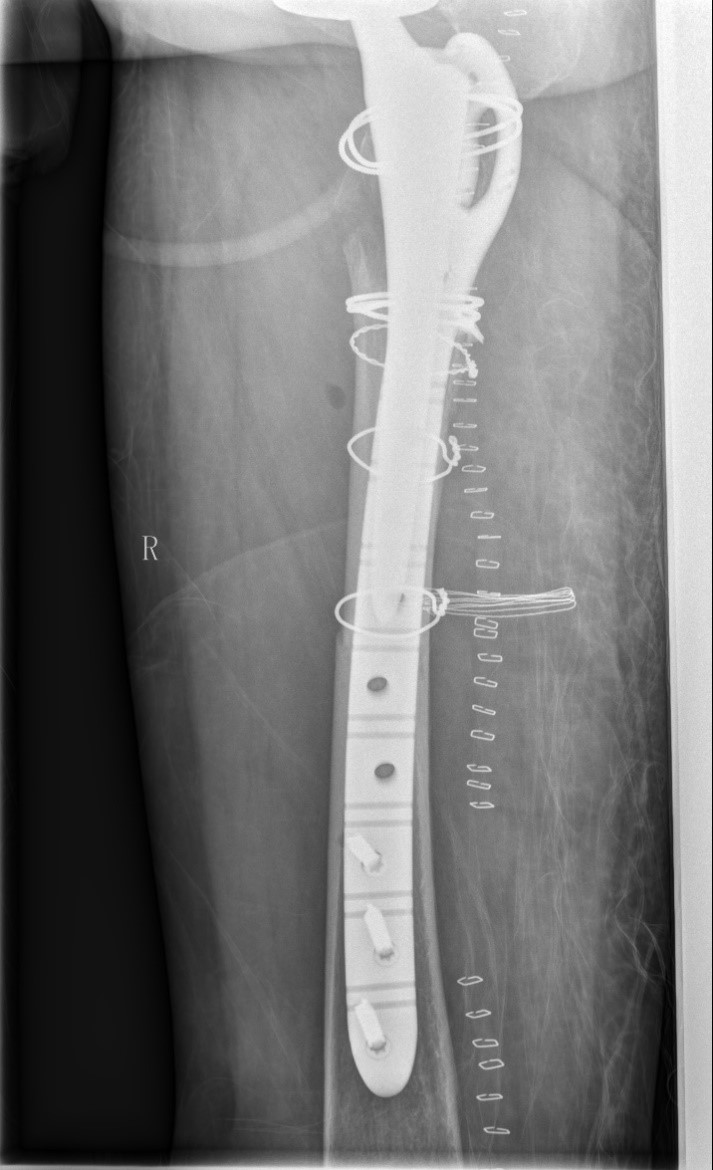

案例三:59岁女性假体周围骨折

患者情况:吴女士,5年前曾在金瓶梅电影接受人工髋关节置换术,近日因在家中地板湿滑处摔倒,导致假体周围骨折。

治疗难点:

1.摔伤后需评估假体是否松动;

2.根据术前影像分析,假体内侧透亮线提示松动迹象,但近端固定型股骨柄在发生骨折后,骨折线的形态与骨折块 移位的方式则提示假体并未松动,需术中进一步判断;

3.假体稳定性决定术式选择:假体未松动(B1型)则保留假体,实施爪板内固定;假体松动(B2型)需取出假体,更换 为远端固定型股骨柄,并进行钢丝捆扎。

4.针对手术方案的复杂性与不确定性,需要与患者及家属充分沟通,明确术中可能面临的风险,并取得他们的理解与 信任,才能为手术顺利实施奠定基础。

5. 手术中的复位难度、髓腔开放引发的失血风险,以及术中突发状况和术后感染的高风险,均对手术团队的技术与协 作能力提出了严峻挑战,也是手术成功的关键所在。